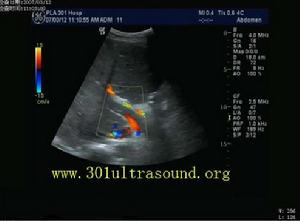

彩色都卜勒顯示門靜脈內血流充盈缺損,周邊見少許血流信號1、實驗室檢查 血液學檢查,急性期病例可有血細胞比容和血紅蛋白增高等多血征表現,血常規檢查可有白細胞增高,但不具特徵性。慢性型的晚期病例,若有上消化道出血或脾大、脾功能亢進者,可有貧血或血小板、白細胞減少。肝功檢查,急性型者可有血清膽紅素增加,ALT、AST、ALP升高,凝血酶原時間延長和血清白蛋白減少,慢性型病例,肝功能檢查多無明顯變化。腹水檢查,若不伴有自發性細菌性腹膜炎,蛋白濃度常低於30g/L,細胞數亦不顯示增加。免疫學檢查,血清IgA、lgM、IgG、IgE和C3等無明顯特徵性變化。

2檢查方法儀器:美國AIL公司生產的HDI-3000型彩色都卜勒超聲診斷儀,凸陣探頭,頻率2~4MHz。患者空腹8~12h,仰臥位、左側臥位、必要時坐位,常規檢查肝臟大小、形態、內部回聲;測量肝靜脈、下腔靜脈內徑;觀察肝靜脈、下腔靜脈是否通暢,有無狹窄,周圍有無腫塊擠壓,腔內有無異常回聲,有無波動。彩色都卜勒及脈衝都卜勒觀察肝靜脈下腔靜脈血流色彩、頻譜形態、血流速度。聲束與血流夾角60°,腹水多者如影響觀察要抽水後複查。

1、布-加氏綜合徵的超聲特點從本組資料觀察布-加氏綜合徵有以下特點:肝靜脈近段狹窄或閉塞,內有膜性或實質性阻塞物,狹窄處血流變細,閉塞時血流消失,遠段血流淤滯擴張,擴張的肝靜脈血流方向異常或速度減慢。肝靜脈間交通支形成、擴張,副肝靜脈開放擴張。都卜勒可見肝靜脈狹窄處呈花彩血流,流速增加,頻譜異常,三相波消失呈平直形。下腔靜脈近心段狹窄或閉塞。表現局部管腔變細、消失,管腔內有膜性、實質性梗阻物或腔外有腫瘤壓迫。下腔靜脈狹窄處近側呈花彩血流,速度增快,本組最高流速達260cm/s,或管腔內無血流信號。狹窄遠側管腔擴張,周圍側支循環豐富,血流方向異常流入側支。下腔靜脈波動消失,頻譜平直。

2、誤診分析本組超聲誤診2例。1例平臥位檢查下腔靜脈近段內徑0.4cm,流速增快250cm/s,坐位時內徑0.55cm,流速100cm/s,肝腫大,肝靜脈擴張,唆水。經保肝利尿治療後,肝臟縮小,腹水消失。複查下腔靜脈內徑0.9~1.0cm,流速100cm/s。最後診斷:酒精性肝硬化。另1例下腔靜脈近心段內徑1.0cm,臥位呈花彩血流,坐位呈單色血流,流速145cm/s,肝明顯腫大,肝靜脈擴張。經治療後肝縮小,腹水及下肢浮腫消失,最後診斷:腎病綜合徵。分析此2例是肝腫大重力後壓引起下腔靜脈狹窄。改變體位,減輕肝對下腔靜脈的壓迫,可使下腔靜脈增寬,流速降低。這種變化可以作為鑑別診斷要點。目前國內有採取俯臥位或近俯臥位經肋間觀察下腔靜脈,但患者往往難以接受。我們認為坐位是一種較好的鑑別診斷方法。另一方面,此2例僅有肝靜脈擴張,未見交通支和副肝靜脈擴張,說明肝靜脈通暢或間歇性通暢,李傑等曾報告布―加氏綜合徵中副肝靜脈的意義,從本組誤診情況來看,觀察肝靜脈交通支特別是副肝靜脈有無擴張對布-加氏綜合徵的鑑別診斷有重要價值.